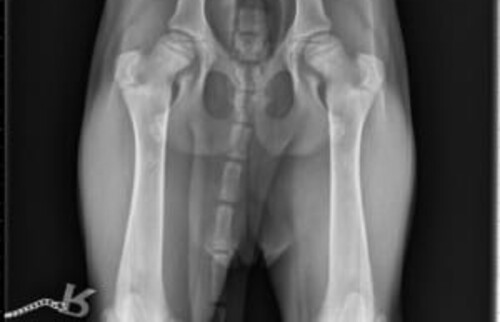

Bilder einer vollständigen Hüftdysplasie-Untersuchung beim Hund

In unserer Tierklinik bei Karlsruhe können unsere Ärzt*innen durch die Aufnahmen eine zuverlässige Prognose für die Weiterentwicklung der Hunde-Hüfte stellen.

Schwarz-weißes Röntgenbild der Hüftgelenke eines Tieres mit abgespreizten Hinterbeinen.